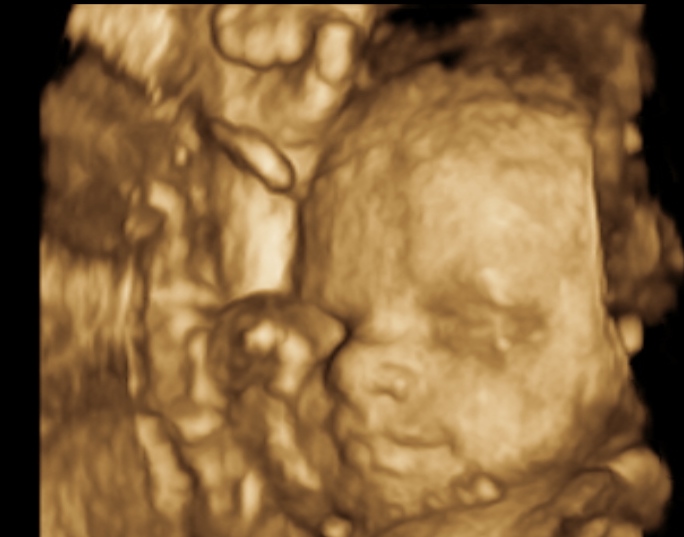

I am 28 weeks this week, so I hit 3rd Trimester. I had an ultrasound last week and we got to see LO. My DH was soo excited because "it" has his nose. I'll attach a picture of him/her at the end of this post. Other than that just gaining weight and my bump is getting bigger.